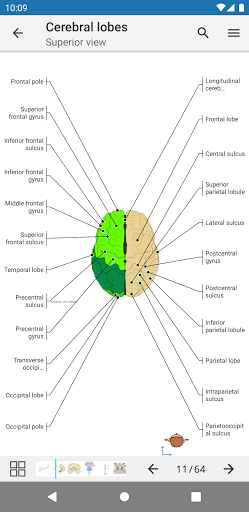

e-Anatomy memiliki lebih dari 26.000 gambar yang berisi serangkaian gambar dalam tampilan aksial, koronal, dan sagital serta radiografi, angiografi, gambar diseksi, bagan anatomi, dan ilustrasi. Semua gambar medis diberi label dengan cermat, lebih dari 967.000 label tersedia dalam 12 bahasa termasuk Terminologia Anatomica Latin.

- Ketuk label untuk menampilkan struktur anatomi

- Pilih label anatomi berdasarkan kategori